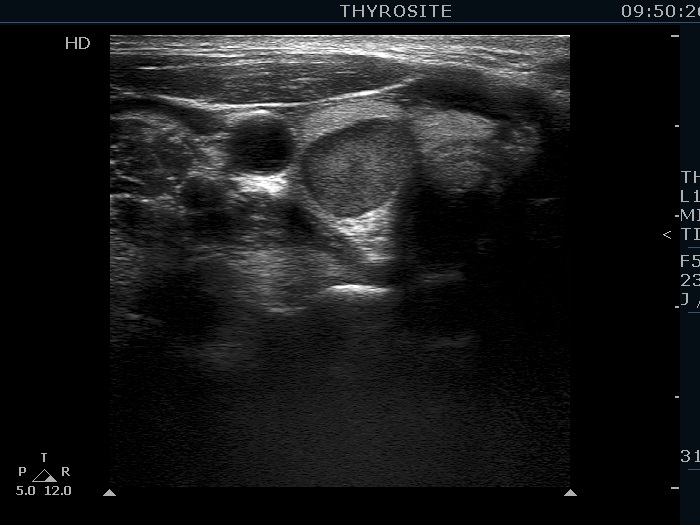

Clinical data: A 43-year-old woman was diagnosed with primary hyperparathyroidism. Scintigraphy disclosed an enlarged right lower parathyroid. The initial cause of evaluation was elevated serum calcium level detected by chance. The patient was referred in order to confirm and to accurately localize the lesion before surgery.

Ultrasonography. The thyroid was echonormal. There was a hypoechoic mass within the lower pole of the right lobe. The lesion was surrounded by thyroid tissue throughout.